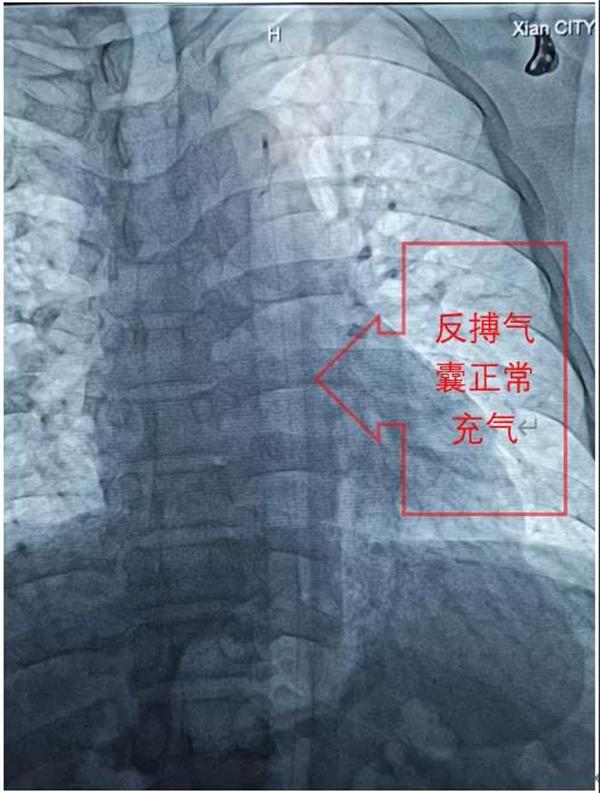

在刘毅龙主治医师的协助下,张拓伟副院长短时间顺利完成反搏球囊置入,随后韩延琪护师娴熟地完成连通管路,并精细调整反搏心电/血压触发比例,伴随着反搏气囊规律的充排气声,患者血压很快稳定在130/80mmHg左右,病情趋于平稳。随后,在张拓伟副院长的指导下,刘毅龙主治医师顺利完成后续的支架植入、高压后扩张等操作。当一条完整的血管和澎湃的血流重新呈现在眼前,患者胸痛症状完全缓解时,所有人紧绷的神经才放松下来,随后韩延琪护师根据心电/血压调整IABP的反搏触发等参数,患者病情稳定并安返病房。